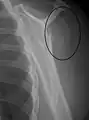

A fracture of the greater tuberosity as seen on AP X ray

A fracture of the greater tuberosity of the humerus

Fracture of the greater tuberosity of the humerus